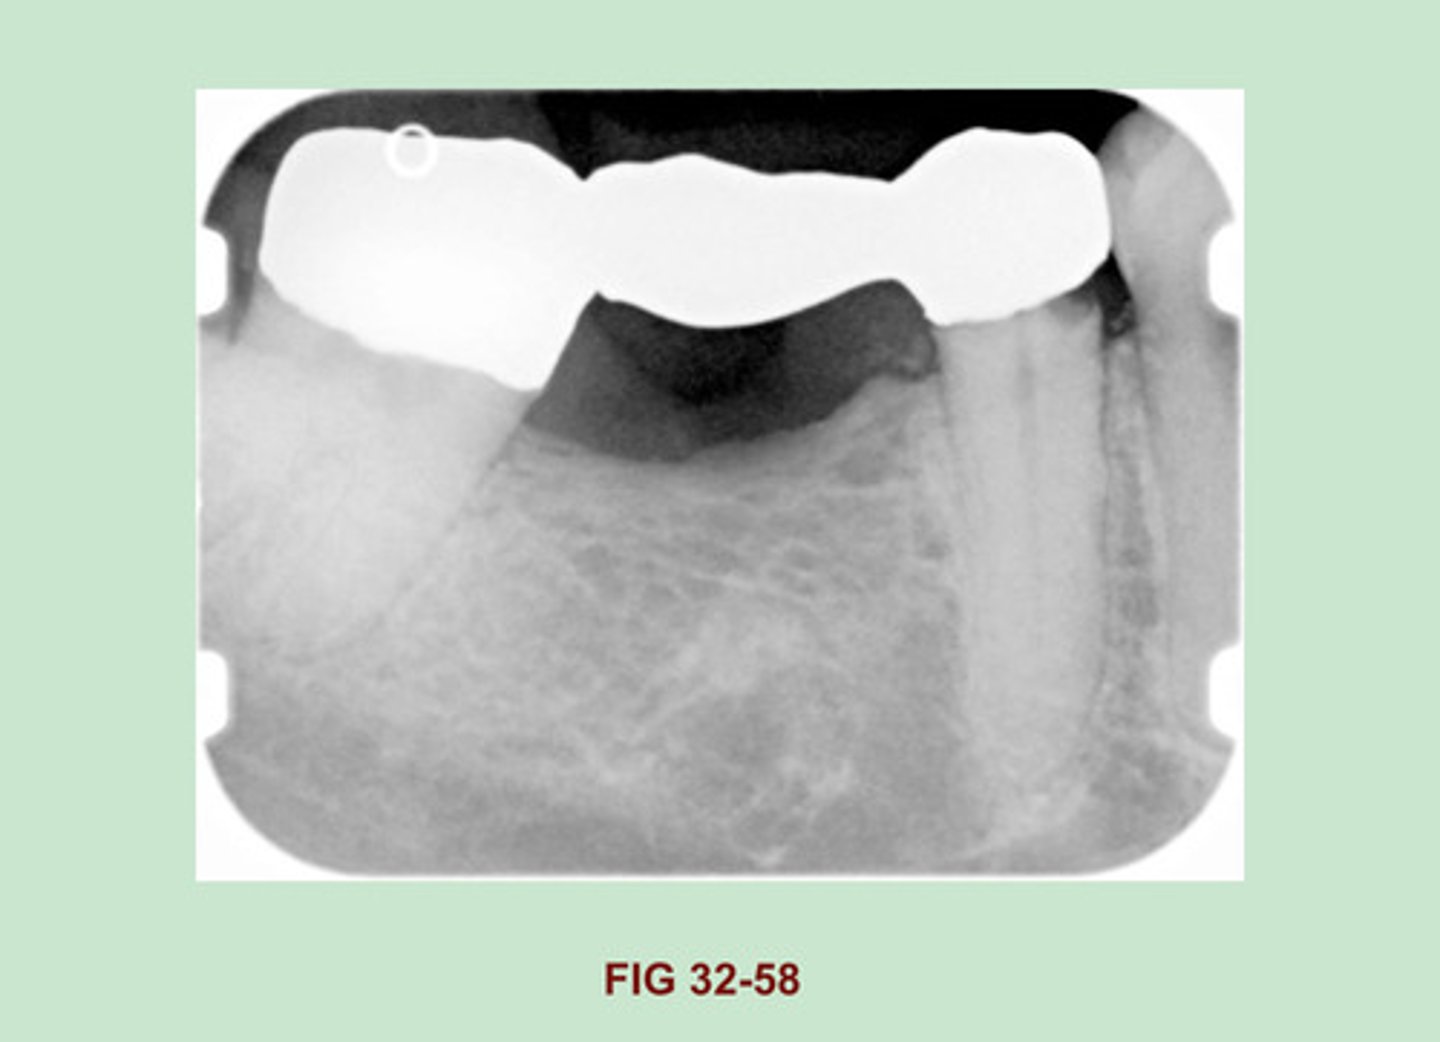

Identify the RESTORATIVE material used to FABRICATE this BRIDGE (Figure 32-58).

Gold bridge

Side Note: Gold crowns & bridges appear as large radiopaque restorations with SMOOTH CONTOURS & REGULAR BORDERS. Similarly, gold inlay & onlay restorations exhibit marginal outlines that appear smooth & regular.